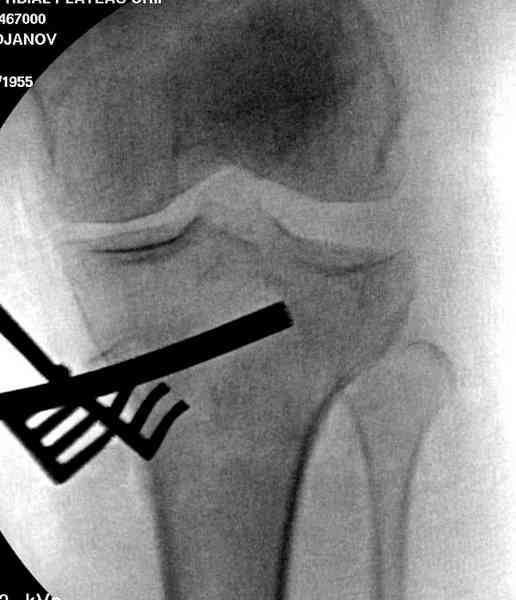

Из медиального окна можно приподнять латеральную

импрессию. Фиксация тремя параллельными шурупами в

эпифизарной части над импрессией. Создается крыша,

которая предупредит коллапс. На образовавшуюся полость - костная пластика из аутокости или синтетический заменитель. Мы применяем Osteoset в 4-5 мм диаметре таблеточки или иньекционную форму Prodens.